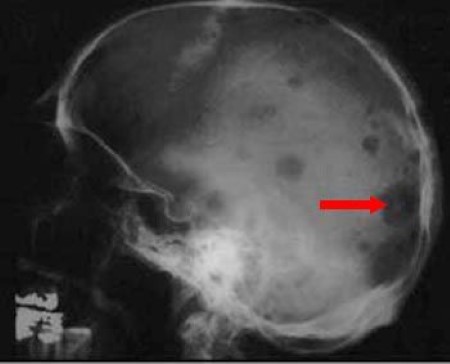

X-ray showing bone lesions in Multiple Myeloma patient

• B — Bone pain/lesions: Seen in 70% of patients, often in the back or ribs.

4. X-rays or MRI — detecting bone lesions.